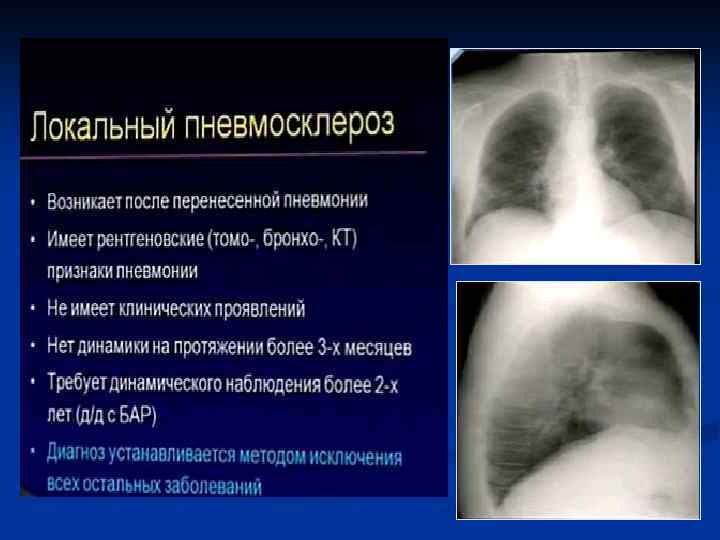

ПН язычковых сегментов Постепенное рассасывание ПН Формировние пневмосклероза

Клиническая картина Типичная - острое начало - лихорадка - кашель с обильной гнойной мокротой, влажные хрипы - боли в грудной клетке Атипичная - постепенное начало - сухой непродуктивный кашель - недомогание - першение в горле - миалгия - головные боли